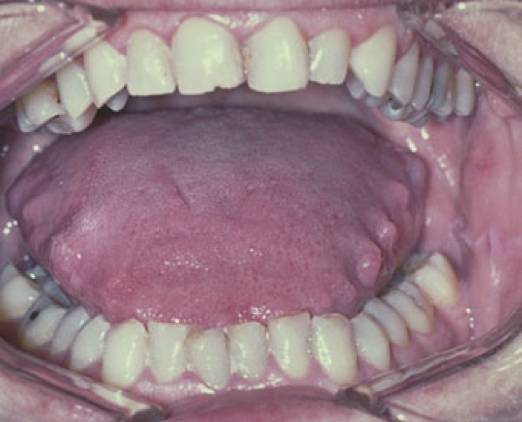

Отпечатки зубов на увеличенном органе

При легкой форме заболевания человек практически не замечает никаких изменений и признаков проблемы. Иногда человек может испытывать дискомфорт. При тяжелых формах болезни речевой орган увеличивается в несколько раз, и он перестает помещаться во рту. Из-за этого человек не может закрыть рот и у него усиливается слюноотделение. На слизистых тканях появляются ранки и шрамы от зубов. Ограничивается подвижность языка, а его поверхность становится шершавой, сухой и покрывается трещинами. Иногда могут появляться водянистые пузырьки.

- В случае, если у пациента опух язык по бокам, особенно когда на боковой поверхности видны отпечатки зубов, врач может заподозрить заболевания щитовидной железы. В этом случае необходимо направить пациента на исследование уровня гормонов щитовидной железы.

Распространенная причина, по которой на языке появляются следы зубов, – это его опухание и увеличение в размере. Это, в свою очередь, тоже симптом, а вот причин у такого явления масса, что затрудняет постановку верного диагноза.

Пациент жалуется на боль и жжение во рту, которые усиливаются во время приема пищи. Эрозии со временем перерастают в язвы, может начаться некроз слизистой. Язык увеличенный и отекший, поэтому по бокам и на щеках могут появляться отпечатки зубов.